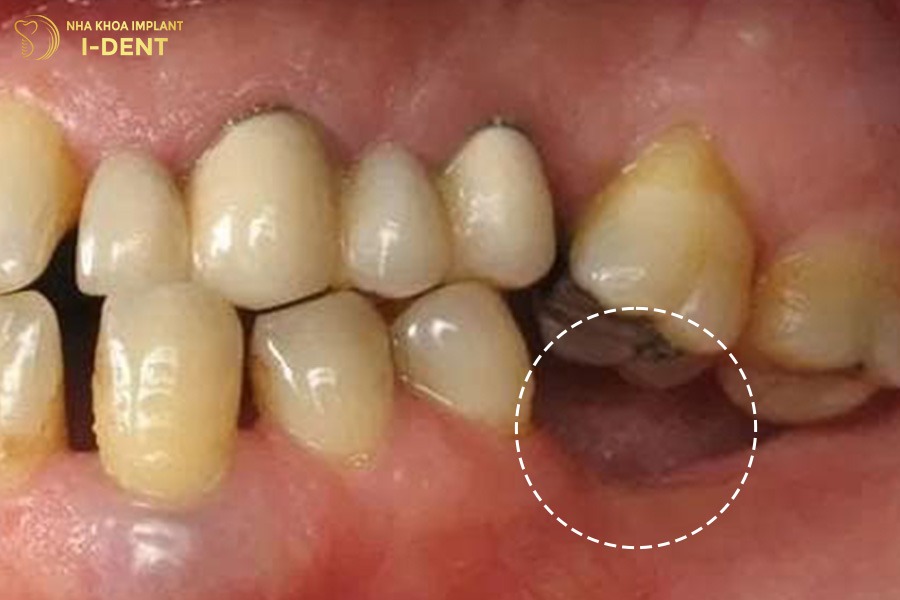

4.2. Phương pháp trồng răng implant

Trồng răng implant là quá trình cấy ghép trụ implant nhân tạo làm bằng titanium vào xương hàm để thay thế chân răng thật đã mất. Sau đó, bác sĩ sẽ mão răng sứ lên trụ này thông qua một khớp nối (abutment) để tạo thành một chiếc răng hoàn chỉnh, khôi phục hoàn toàn chức năng ăn nhai và thẩm mỹ cho bệnh nhân.

Ưu điểm

- Phục hồi toàn diện cả chân răng và thân răng nên mang lại cảm giác nhai tự nhiên như răng thật.

- Ngăn ngừa tiêu xương hàm hiệu quả.

- Không cần mài răng kế cận nên bảo tồn răng thật tối đa.

- Tuổi thọ cao, có thể sử dụng trọn đời nếu chăm sóc tốt.

- Đảm bảo tính thẩm mỹ cao, khớp cắn ổn định và bền vững lâu dài.

Nhược điểm

- Chi phí cao hơn so với các phương pháp khác.

- Thời gian điều trị kéo dài, mất 2-6 tháng để trụ implant tích hợp hoàn toàn với xương hàm.

- Cần được thực hiện bởi bác sĩ chuyên khoa có tay nghề cao và trang thiết bị hiện đại để đảm bảo an toàn.

Trồng răng implant để phục hình răng số 6 đã mất lâu năm.